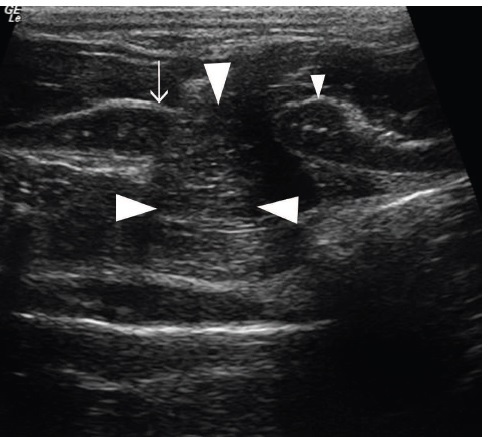

Fig 8: Comparison of echogenicity of the cricoarytenoideus lateralis and vocalis (arrows)

and cricoarytenoideus dorsalis (arrowheads) musculature. Horses with recurrent

laryngeal neuropathy have increased echogenicity and more homogeneous echogenicity

of the cricoarytenoideus lateralis and cricoarytenoideus dorsalis muscles. Dorsal plane

ultrasound images of the cricoarytenoideus lateralis muscle of (a) a horse with recurrent

laryngeal neuropathy and (b) a normal horse. Transverse plane ultrasound images of the

cricoarytenoideus lateralis and vocalis muscles of (c) a horse with recurrent laryngeal

neuropathy and (d) a normal horse. Dorsal plane ultrasound images of the cricoarytenoideus

dorsalis muscle of (e) a horse with recurrent laryngeal neuropathy and (f) a normal horse. In

the dorsal plane images, rostral is to the left and caudal is to the right and in the transverse

plane images, dorsal is to the left of the image and ventral is to the right